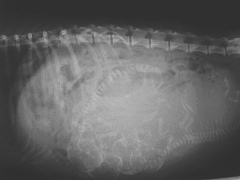

上からみたレントゲンと

横からみたレントゲン

病院でレントゲン写真を撮っていただきました。

産道と胎児の頭の大きさチェックです。普通分娩が可能であるかの確認のためです(産道の幅より頭が極端に大きいと帝王切開の確率が増えます)。

なんと4匹の胎児が順調に育っていました。よんひき!・・・・・・・・・・・・。

上から撮ったレントゲンです。中央がまめの背骨。左右に小さい4匹分の背骨と頭が見えます。右の子宮に2匹、左の子宮に2匹です。

横から撮ったレントゲンです。右がお尻のあるほうです。

2匹(産道側)が逆子です。そのため4匹が頭をくっつけている状態でお腹におさまっています。お腹の下の方に4匹の頭が重なっているのがわかりますか?

なんだか、4匹でひそひそ相談しているように見えます(笑)。

産道より胎児の頭の方が小さいので、今週中に生まれるとすれば順調な出産になるそうです。

4匹もいるので、あまりおおきく育っていないようです。産むのは楽かも。